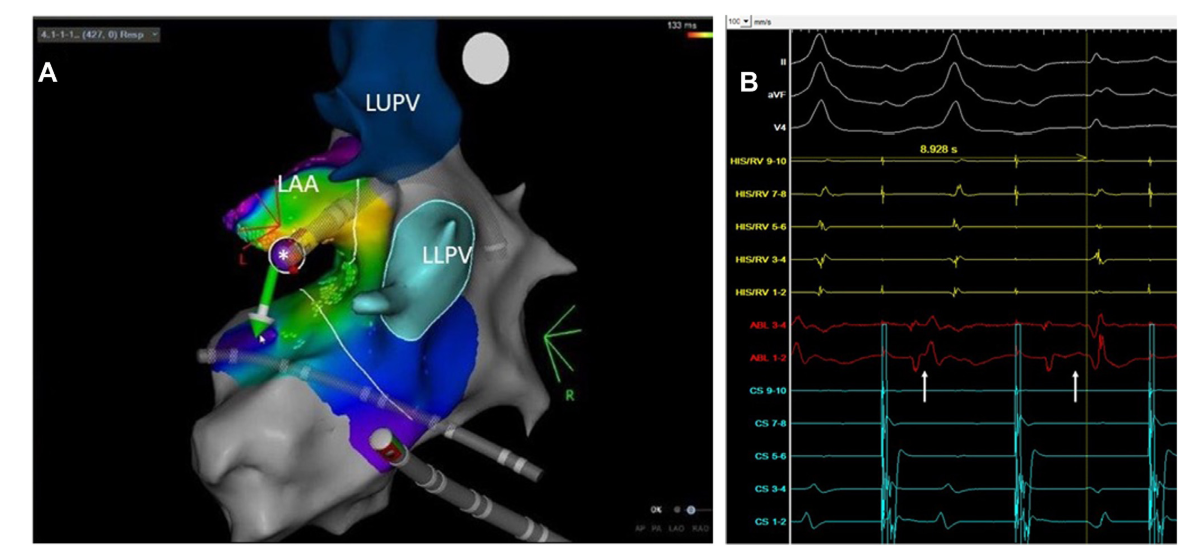

LA-CS potentials

epicardial_ap_signal_sequence.jpg

la_cs_block.jpg